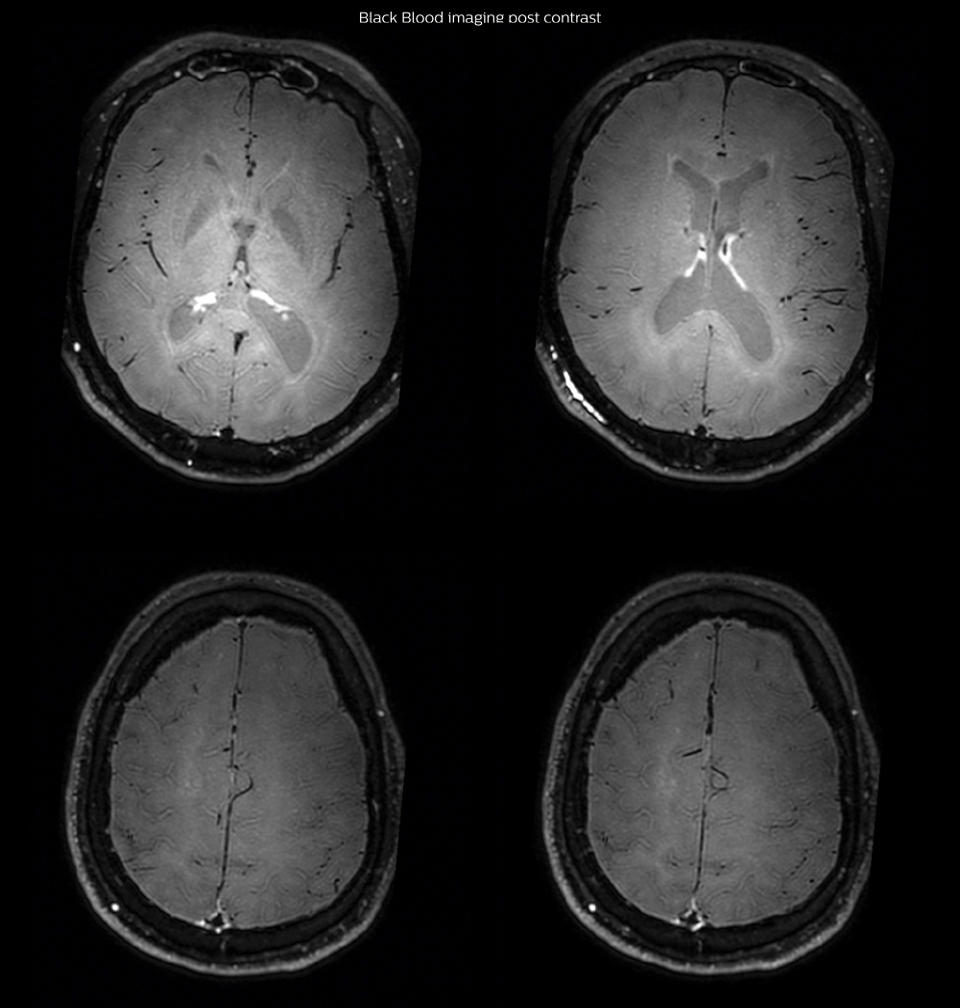

On FLAIR images we can see some nonspecific high signal abnormalities in frontal white matter bilaterally. On DWI we can see acute ischemic lesions which appear with high signal intensity. Arrows show vessel wall enhancement which appears concentric and homogeneous in different cerebral territories.

had, such as glucose intolerance, arterial hypertension and hypocholesteremia, his lesions could be atherosclerotic lesions or vasculitis, conditions which require different treatment. Especially in this patient with HIV infection causing the vasculitis, treatment of the two conditions is different. The results of MRI with Black Blood imaging, helped to choose the preferred treatment for this patient, which was based on antiviral medication rather than an antiaggregant or anticoagulation treatment which is usually given to patients with risk of ischemia based on atherosclerotic lesions. One month after beginning the antiviral treatment, the same MRI examination was repeated and again 8 months after the beginning of treatment. On follow-up images, we see the enhancements have almost disappeared. So in case of this patient, the MRI exam with Black Blood imaging helped us to give the patient the appropriate treatment and also allowed us to noninvasively confirm the treatment response.

After one month of treatment, post-contrast Black Blood images at the exact same levels as in the figure above show disappearance of the vessel wall enhancements which were seen on the previous examination.